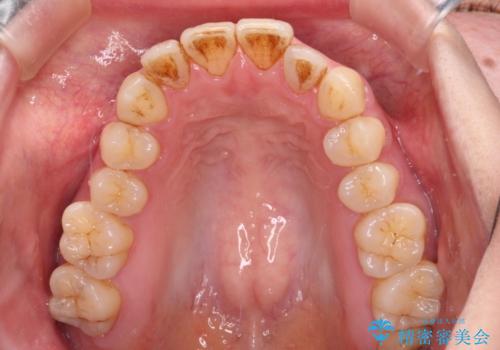

- 上下前歯の隙間を気にして来院された患者様です。

下顎前歯が1本欠損しており、上下小臼歯はクロスバイトとなり、上下前歯の接触もないという不正咬合の状態でした。

クロスバイトはワイヤー矯正が得意とするところであり、上下前歯の非接触や開咬はインビザラインの得意とするところであるので、ワイヤー装置により事前にクロスバイトを改善し、その後にインビザラインにて仕上げていくこととしました。